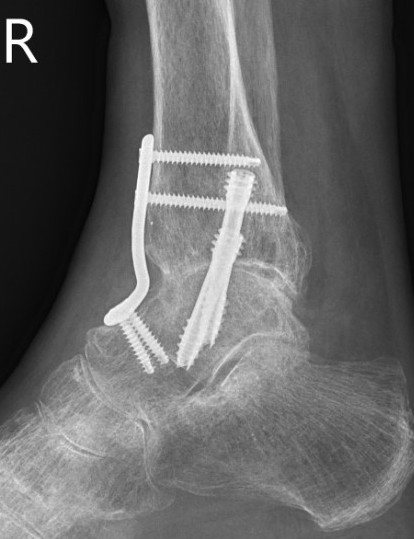

Fixation

- position foot, check with image intensifier

- +/- bone graft

- two cannulated screws from medial tibia to talus dome / neck

- +/- screw medial malleolus to talus

- +/- screw fixation fibular / onlay graft

- fix with 3 x 6.5 mm cannulated screws

- 2 medial and one lateral